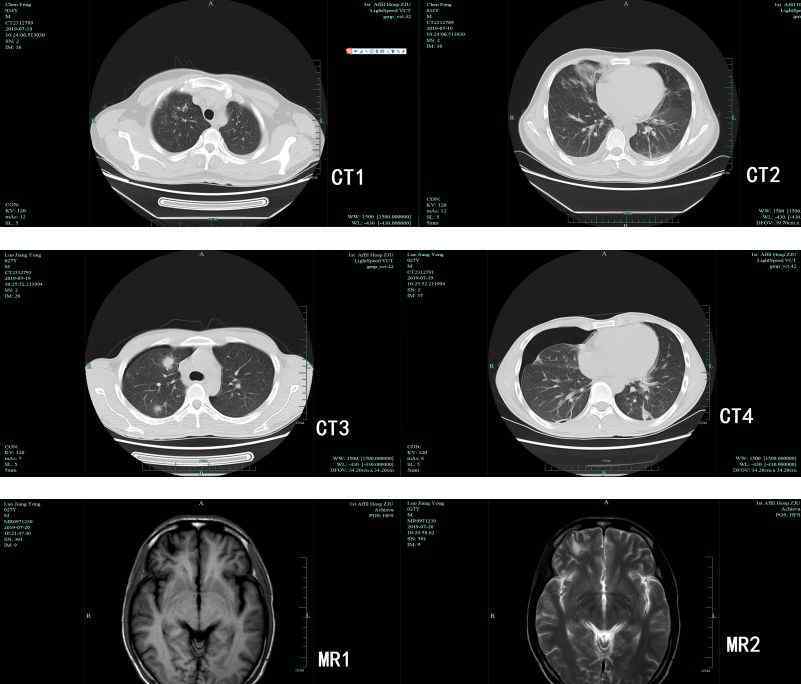

果然,寄生虫检测后,两人都是卫氏并殖吸虫抗体阳性,两人都在腹部和肺部发现了并殖吸虫。罗在脑中发现并殖吸虫囊状病灶,病情较重。好在他们及时发现,及时去了医院,医疗痊愈,没有留下后遗症。

根据主要器官的不同,可分为胸肺型、腹肺型、皮肤型和脑型四种。肺是卫氏并殖吸虫最寄生的部位。卫氏并殖吸虫常引起皮下结节,部分为游走性结节。